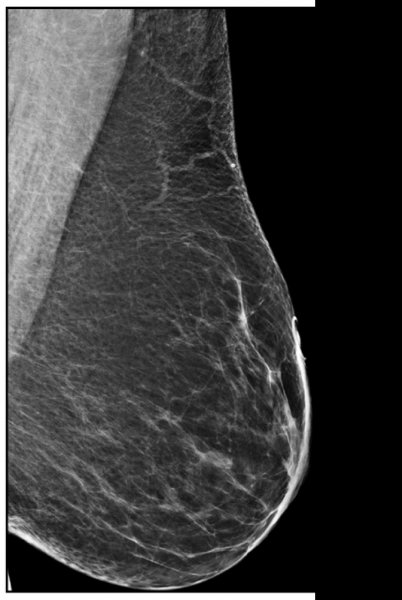

Figure 1. R MLO view from four different years. The skin mole is marked with a circular skin marker (TomoSPOT REF# 782, Beekley Medical) on the far-left image. These images demonstrate the potential for significant variability in location of the skin lesion due to movability of the skin during positioning.

Moles which are further out on the breast can be represented in significantly different locations as shown in Figure 1.